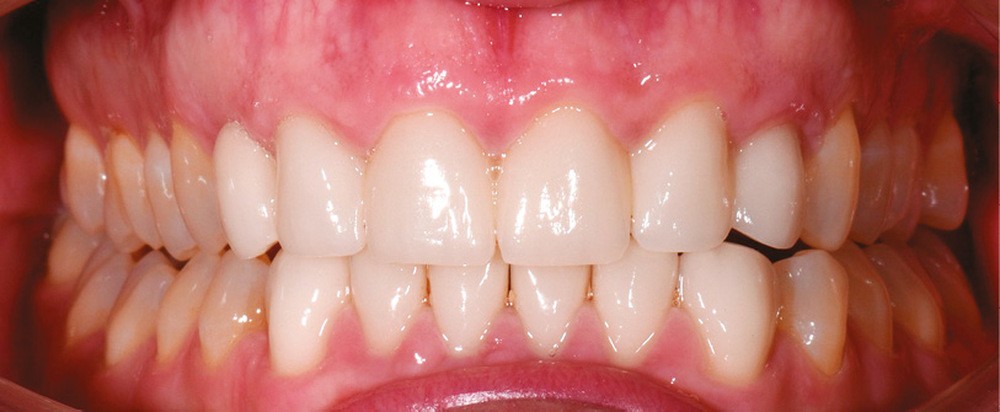

À l’examen endobuccal de première consultation (fig. 1), nous notons la présence d’un bridge maxillaire céramo-céramique sur infrastructure en zircone avec 12, 11, 21 et 22 couronnes moyens d’ancrage et 13 et 23 intermédiaires de bridge en extension. Les incisives et canines mandibulaires ont également été couronnées individuellement. Le patient nous informe que ces soins ont été réalisés pour répondre à sa demande esthétique. L’examen radiologique (fig. 2) révèle la présence de deux canines maxillaires incluses et nous montre qu’aucune dent n’a subi de traitement endodontique.